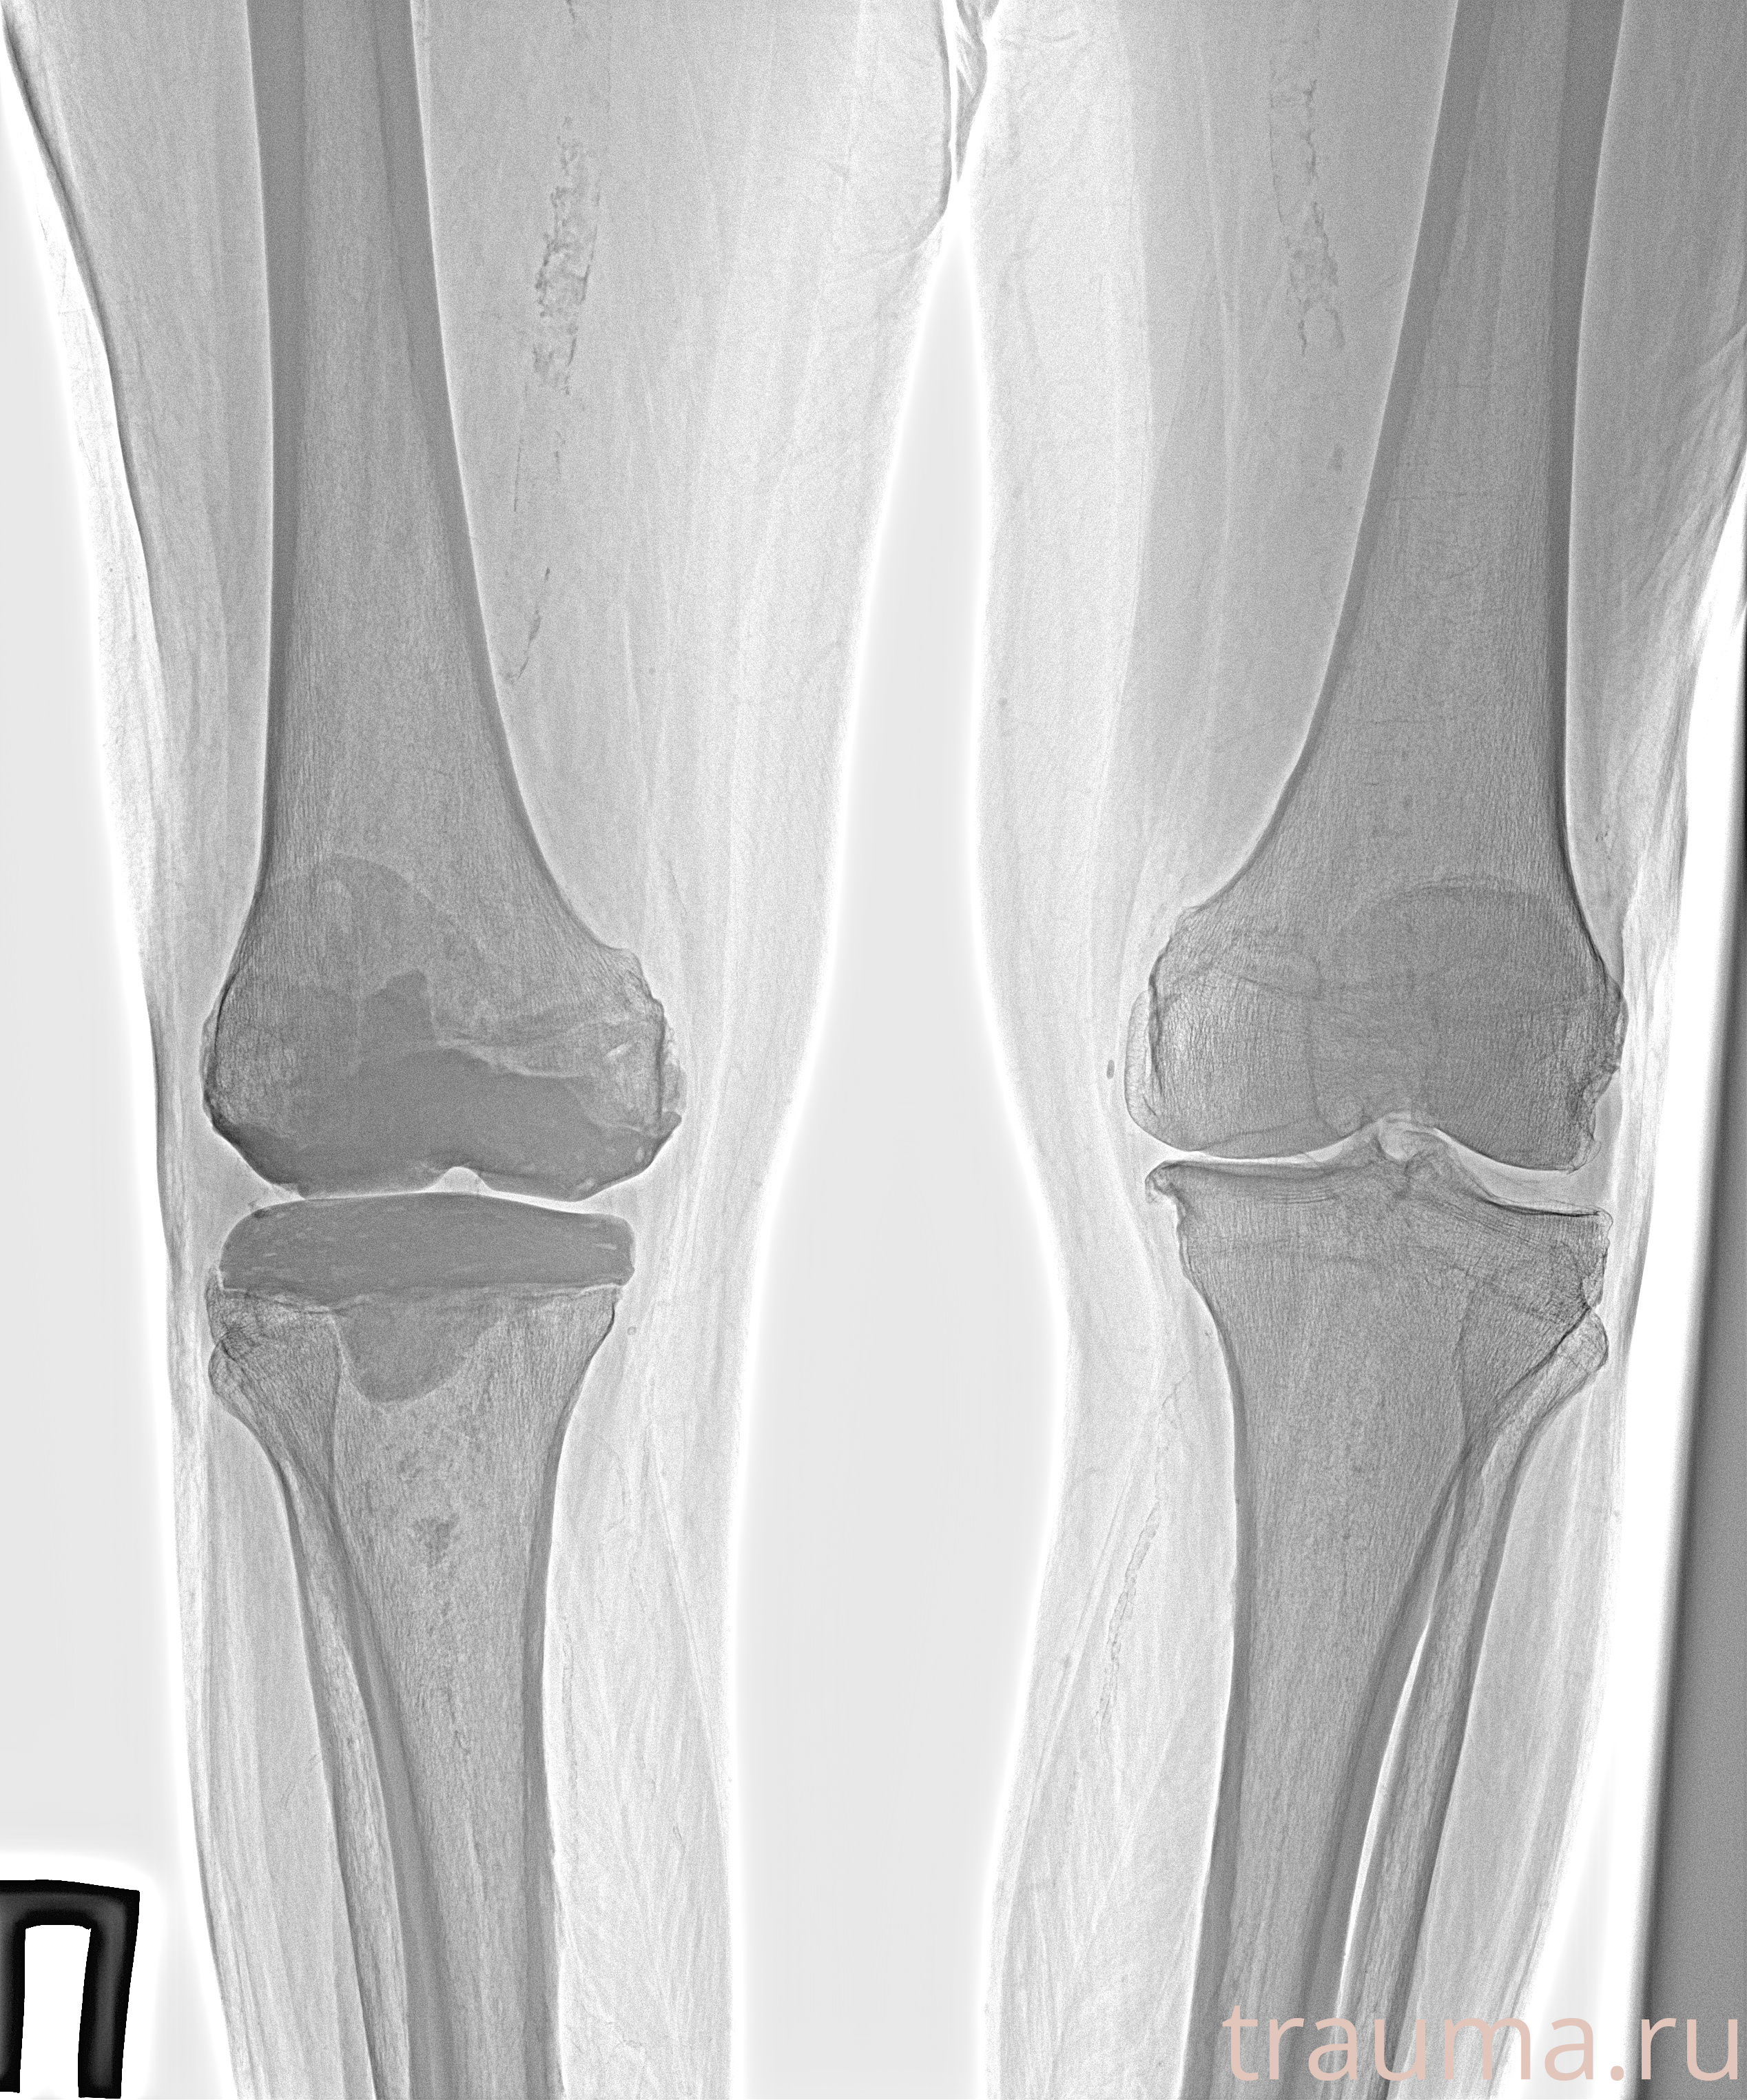

Рентген на дому: по вашему адресу приезжает врач-рентгенолог, травматолог-ортопед с мобильным рентгеновским аппаратом, проводит диагностику травмы или заболевания, делает необходимые рентгенограммы, дает рекомендации по дальнейшему лечению. Получить качественные снимки в домашних условиях возможно благодаря уникальной методике, разработанной МосРентген Центром для института  Склифосовского